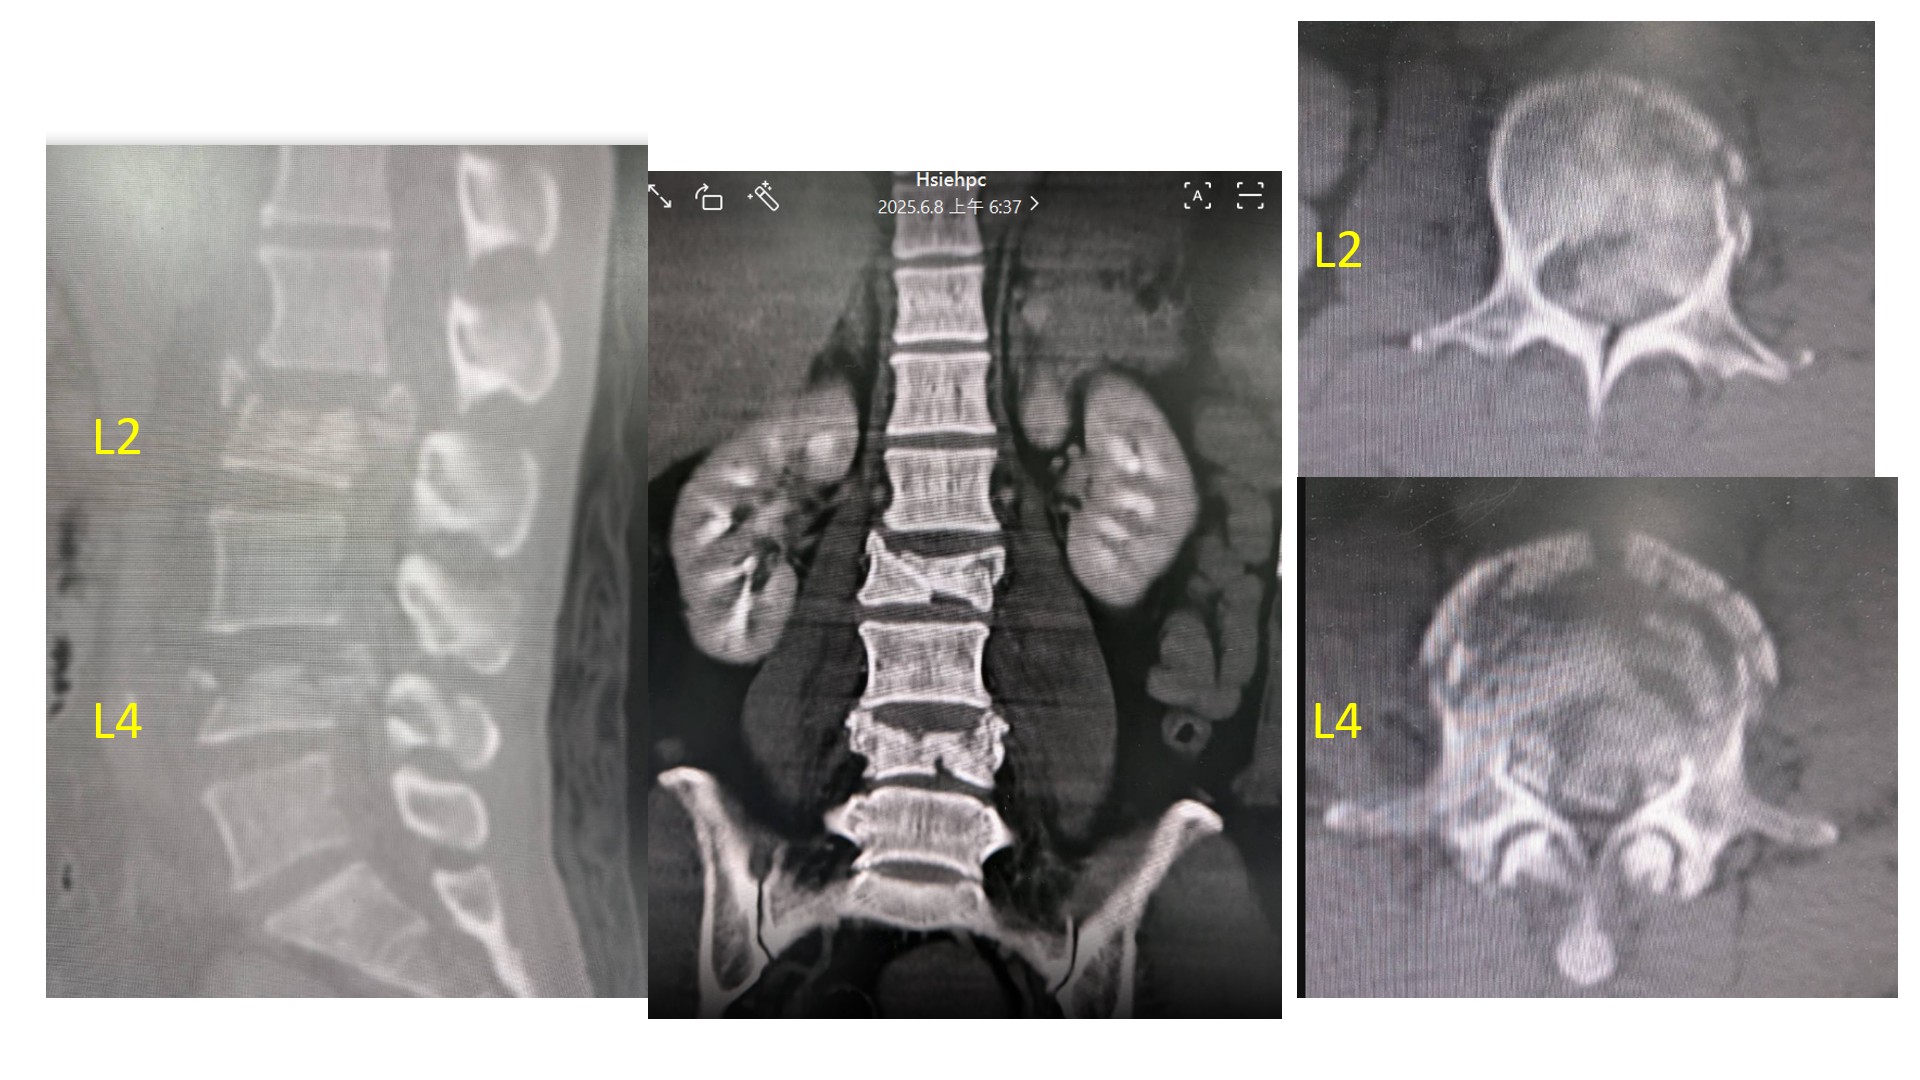

烏日林新醫院骨科謝博欽主任表示,根據劉姓婦人的電腦斷層檢查顯示,第二及第四腰椎出現爆炸性骨折,且椎骨碎片擠壓脊椎孔僅剩10%的空間,另外合併有右手腕橈骨骨折、左手肘脱臼合併橈骨頭骨折、左跟骨骨折、左骨盆恥骨骨折,傷勢極為嚴重。此外更有鋭物插入右臀部深達15公分的穿通傷,所幸未傷及肛門與膀胱。當下只剩腳趾尚能活動,臨床上呈現「脊髓圓錐症候群合併馬尾症候群」,屬於不完全脊髓損傷,情況相當危及若未把握黃金時間盡快進行手術,極有可能演變為永久性癱瘓。

手術過程於每節脊椎置放2支千斤頂,單支可有100公斤的支撐力,千斤頂單支手術傷口僅1公分,出血量不到10C.C.,每節椎體放置2支便具有高達200公斤向上撐開的力量。劉姓婦人共於第二及第四腰椎放置4支千斤頂,同時也接續進行右腕,左肘骨折及臀部傷口手術,術後疼痛極其輕微,隔天就能立即進行復健訓練。相當積極復健的她,術後一個月就能使用助行器練習走路,且能正常大小便,三個月後完全恢復,非常開心能夠重拾正常生活。